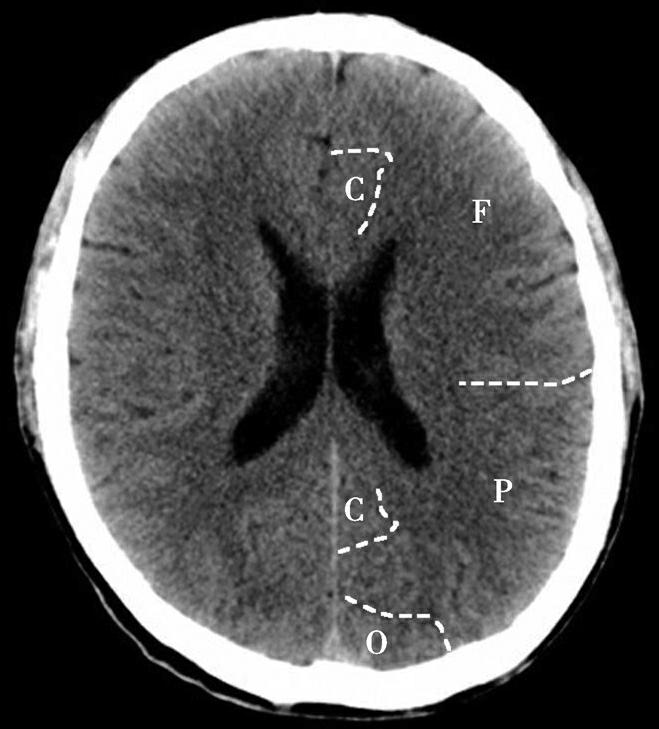

Alberta卒中项目早期CT评分(Alberta stroke program early CT score,ASPECTS)是一种评价急性缺血性卒中患者大脑中动脉供血区早期缺血性改变的简单、可靠、系统化的方法,是常用的脑卒中评定量表之一,可对缺血性病变快速进行半定量评价,有助于判定溶栓效果和远期预后。该评分主要基于CT平扫,具体分区如下(图1-2-76)所示,即选取大脑中动脉供血区2个层面。分区后共10个区域,每个区域记1分。评分时任何区域只要有低密度灶,则扣除该区域得分。正常脑ASPECTS评分为满分(10分),若MCA供血区广泛梗死累及全部区域时,则ASPECTS评分为0分。

图1-2-76 ASPECTS评分脑组织分区

A.在基底节层面(即丘脑和纹状体平面),分为各级分支M 1 、M 2 、M 3 、岛叶(缩写I)、豆状核(缩写L)、尾状核(缩写C)和内囊(缩写IC)后肢等7个区域;B.在基底节以上层面(基底节层面上2cm),包括M 4 、M 5 和M 6 。